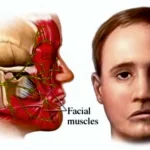

হেমিফেসিয়াল স্প্যাজম (Hemifacial Spasm) হেমিফেসিয়াল স্প্যাজম (Hemifacial Spasm) হলো একটি স্নায়ুতন্ত্রের অবস্থা যেখানে মুখের একপাশের